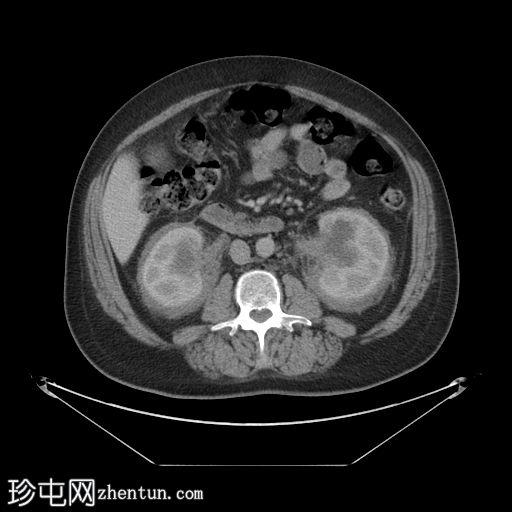

冠状位增强扫描(门静脉期)

肾周可见重度、相对均匀的浸润,呈“毛肾征”。肾积水,但无输尿管积水。

肝、脾、胰腺和肾上腺正常。胆囊正常,无胆管扩张。

小肠和大肠(包括阑尾)未进行肠道准备,均正常。

未见其他异常。